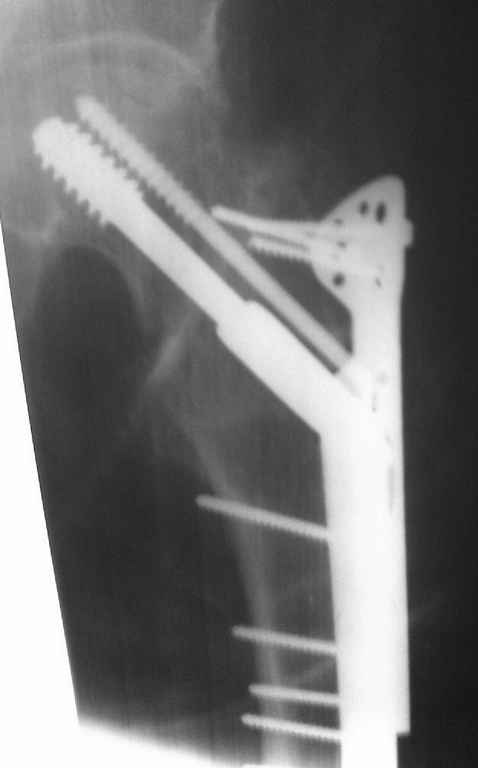

Re: Перелом шейки бедра, 28 лет

Безусловно надо оперировать. Метод фиксации лучше выбрать такой которым Вы лучше владеете, и который позволяет техническое оснащение вашего учереждения. Я бы поставил DHS с деротационным винтом, возможно и без вертельной накладки.